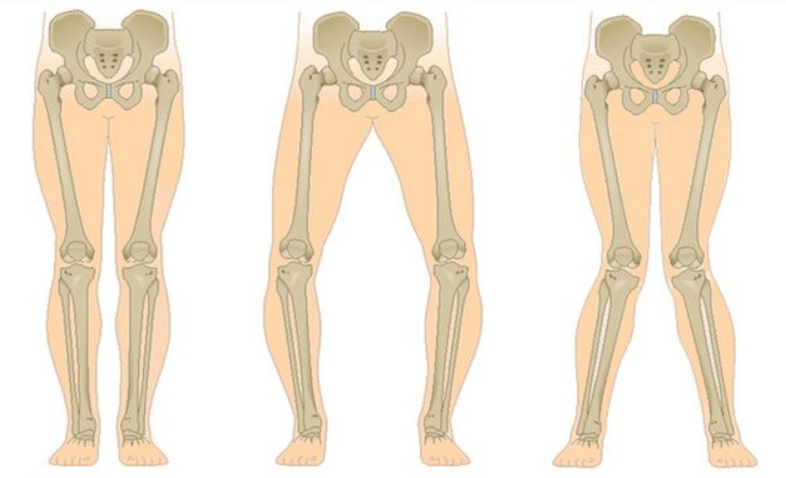

The last stage of gonarthrosis is distinguished by the fact that the pain becomes almost constant, causing anxiety not only while walking, but also at rest, and even at night, when patients have to look for a comfortable position to sleep.Movement is more limited: it is difficult to fully bend and straighten the leg.The joint deforms and increases in volume.Valgus (X-shaped) or varus (O-shaped) deformity of the feet is often observed.Walking becomes unsteady and wobbly.In severe cases, a cane or crutch is needed.

With arthrosis (osteoarthrosis), in addition to the progressive destruction of cartilage, the loss of its elasticity and shock-absorbing properties, the bones are gradually involved in the process.Under load, sharp edges (exostoses) appear, which are mistakenly considered "salt deposits" - with classic arthrosis, salt deposition does not occur.As osteoarthritis progresses, it continues to "eat away" the cartilage.Then the bone is deformed, cysts are formed there, all joint structures are affected and the leg bends.